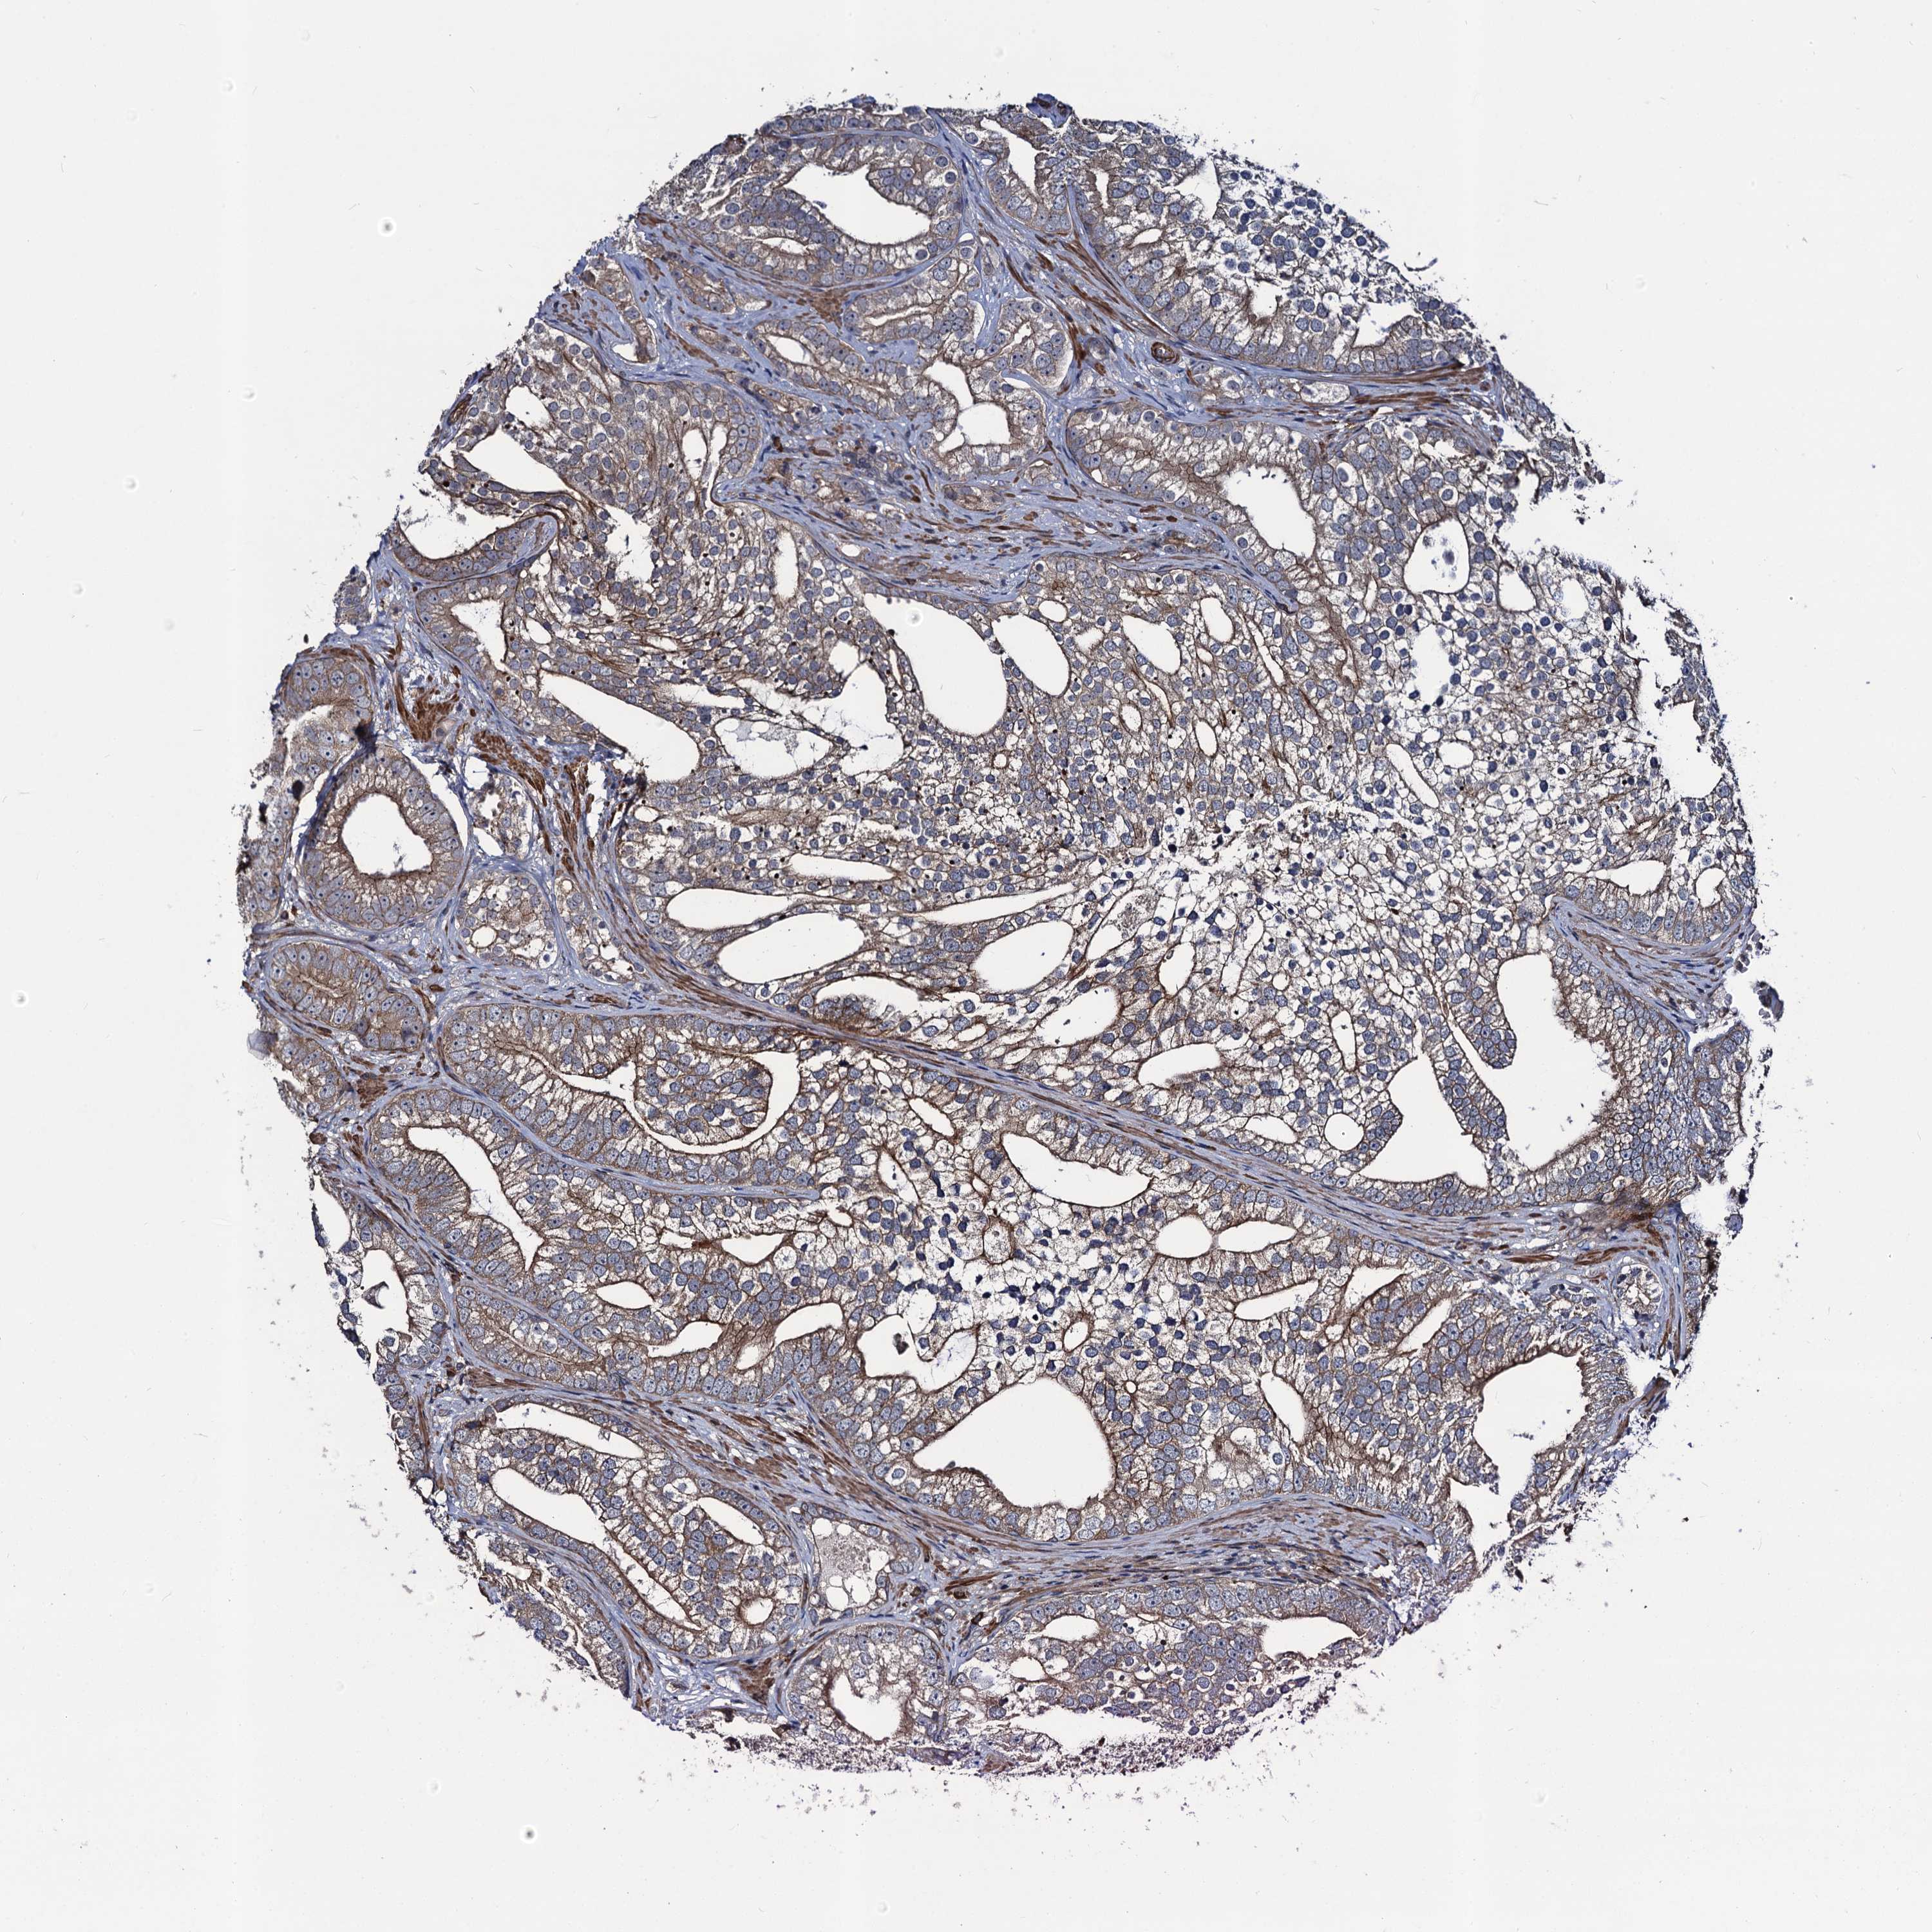

PROSTATE CANCER - Protein expressioni

A mouse-over function shows sample information and annotation data. Click on an image to view it in a full screen mode. Samples can be filtered based on level of antibody staining by selecting one or several of the following categories: high, medium, low and not detected. The assay and annotation is described here.

Antibody stainingi

Antibody staining in the annotated cell types in the current human tissue is reported as not detected, low, medium, or high, based on conventional immunohistochemistry profiling in selected tissues. This score is based on the combination of the staining intensity and fraction of stained cells.

Each image is clickable and will lead to virtual microscopy that enables deeper exploration of all samples and also displays staining intensity scores, fraction scores and subcellular localization as well as patient and tissue information for each sample.

Antibody HPA041507

Antibody HPA041599

Staining

High

Medium

Low

Not detected

Intensity

Strong

Moderate

Weak

Negative

Quantity

>75%

75%-25%

<25%

None

Location

Nuclear

Cytoplasmic/membranous

Cytoplasmic/membranous,nuclear

Adenocarcinoma, High grade

Adenocarcinoma, Low grade

Adenocarcinoma, NOS